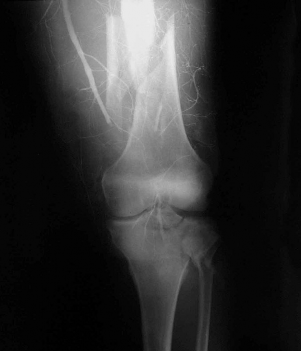

- Chụp động mạch

Năm 1953 Sven-Ivar Seldinger (1921-1998) (trích từ [36],[70]) một nhà điện quang Thụy Điển đã báo cáo mô tả kỹ thuật chọc kim qua da để đặt catheter và tiêm chất cản quang vào động mạch qua đó chụp thăm dò tổn thương mạch máu do bệnh lý. Từ đó kỹ thuật này mang tên là Seldinger. Kỹ thuật chụp này sử dụng loại thuốc cản quang chứa Iod không Ion hoá, tan trong nước, rất ít tai biến và có độ nhạy và đặc hiệu cao (94% - 100% và 86%

- 98%) [36],[70] nên chụp động mạch được coi như một tiêu chuẩn vàng để chẩn đoán tổn thương động mạch.

Các hình ảnh tổn thương của chụp động mạch có thể là tắc động mạch (ảnh 1.5), co thắt hoặc khuyết cản quang do đụng dập nội mạc[86].

Ảnh 1.5: Hình ảnh tắc động mạch khoeo kết hợp gãy 1/3dưới xương đùi trên phim chụp động mạch.

⃰ Nguồn: theo Perron A.D. và cộng sự (2001)[86]